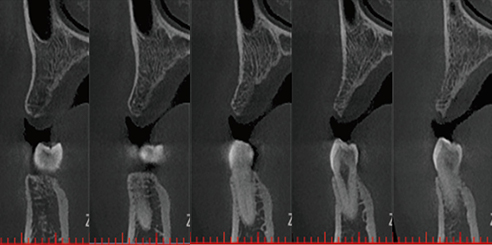

High-Resolution Dental CBCT Imaging

The system achieves image resolutions up to 2.0 lp/mm with a voxel size range of 0.05 – 0.25 mm.

Its 0.5 mm small focus tube guarantees smooth, stable, and reliable scans.

Furthermore, the high-definition image output ensures accurate diagnosis and confident treatment planning.

0.5mm small focus tube ensures outstanding image quality.

Resolution up to 2.0lp/mm, voxel size of 0.25~0.05 mm optional.